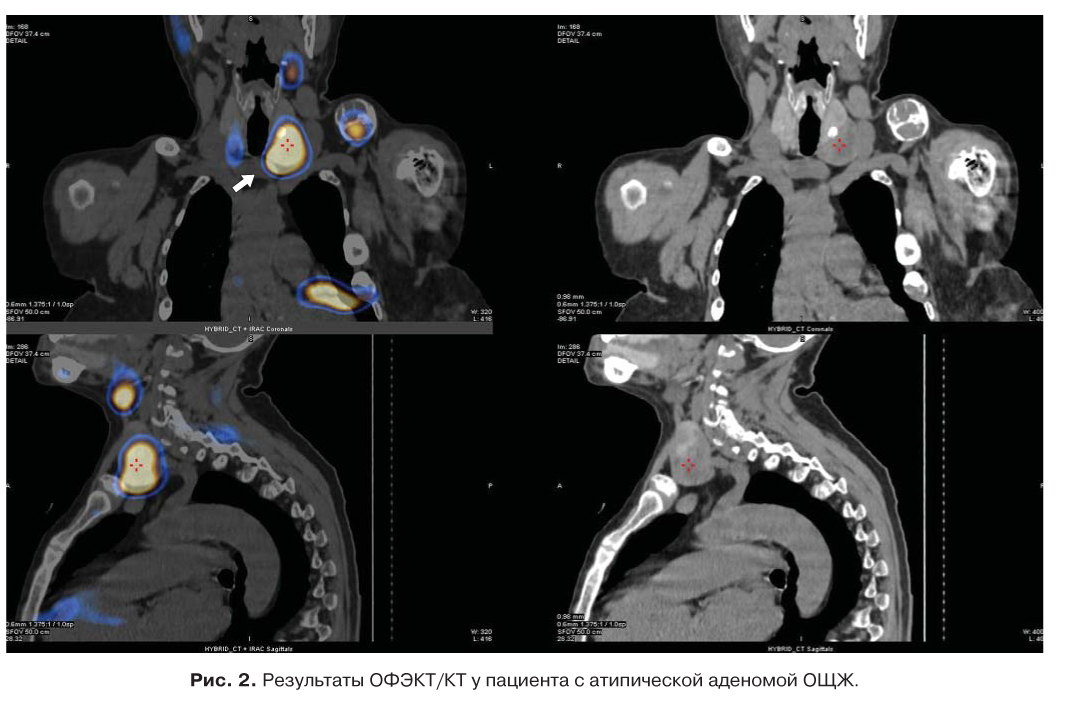

С целью топической диагностики выполнено: УЗИ ОЩЖ – визуализировано образование левой нижней ОЩЖ размерами 4,6 × 4,2 × 3,1 см пониженной эхогенности с жидкостными зонами, образование правой нижней ОЩЖ размерами 0,7 × 0,3 × 0,3 см; сцинтиграфия ОЩЖ c 99mТс-технетрилом (MIBI) в режиме ОФЭКТ/КТ, определялось образование с четкими контурами, размерами 4,3 × 3,4 × 4,0 см, активно накапливающее РФП позади средней и нижней трети левой доли щитовидной железы, распространяясь книзу от нижнего полюса. Позади нижней трети правой доли – образование размерами 0,8 × 0,4 × 0,6 см, с низкоинтенсивным накоплением РФП (рис. 1, 2). Результаты сканирования с MIBI подтвердили наличие одного образования ОЩЖ с характерным поражением костей.

Рис. 2. Результаты ОФЭКТ/КТ у пациента с атипической аденомой ОЩЖ.